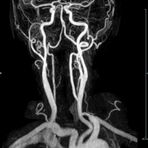

MR-Angiografie (MRA)

Angiographie ohne Kontrastmittel

• MR-Angiografie ohne Kontrastmittel

• Time of Flight (TOF)-Angiographie

• Phasenkontrastangiographie (PCA). Geeignet zur Quantifizierung Stenose-/Insuffizienzgrad z.B. bei Herzklappen, falls echokardiographisch die Untersuchungsbedingungen eingeschränkt sind.

Je nach Fragestellung und Körperregion Gefäßdarstellung ohne Kontrastmittel bei Kontrastmittelunverträglichkeit oder terminaler Niereninsuffizienz möglich.

Ganzkörper Angiographie mit Kontrastmittel

• MR-Angiographie mit Kontrastmittel

• Erfassung arterieller und venöser Gefäße/Bypässe aller Körperregionen mit 3D-Rekonstruktion

• je nach klinischer Fragestellung zeitaufgelöste MR-Angiographie (4D-MRA) z.B. bei Frage arteriovenöse Fistel/ Shunt oder Darstellung Unterschenkelarterien vor geplanter Bypassoperation.